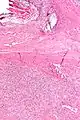

Micrograph of a solitary fibrous tumor. H&E stain. | |

- Solitary fibrous tumor - low magnification. H&E stain.

- Solitary fibrous tumor - high magnification. H&E stain.